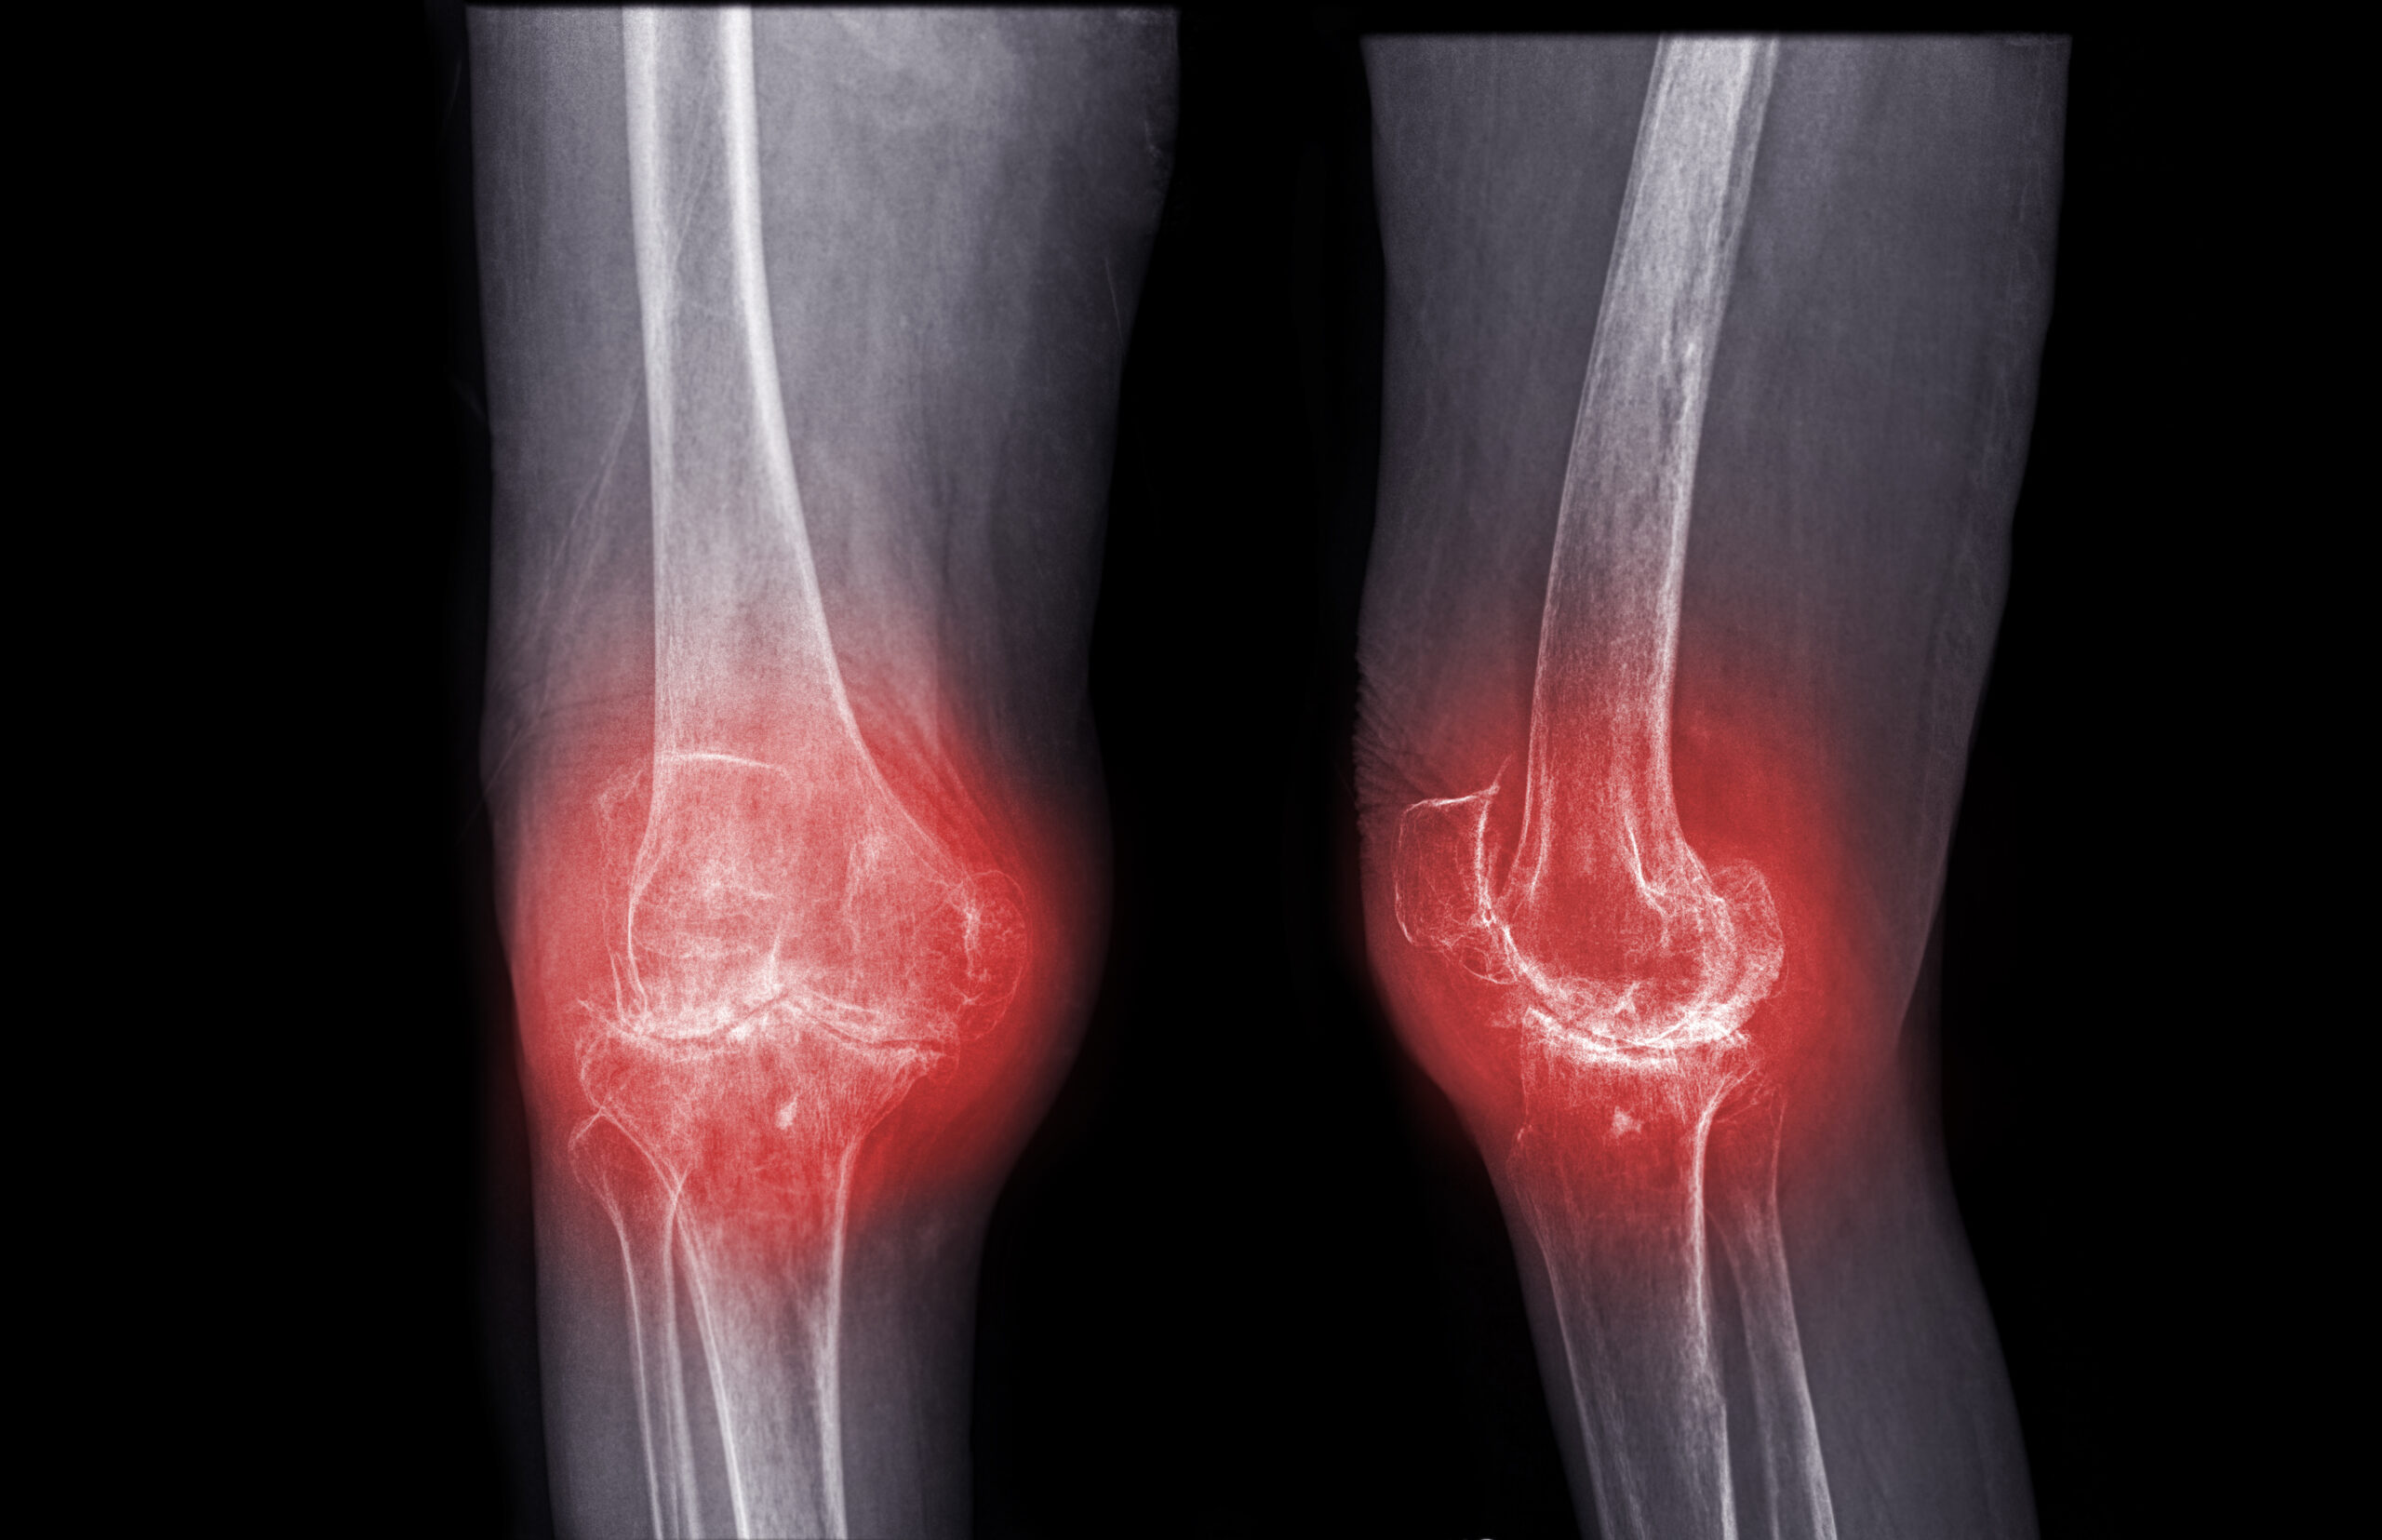

Sometimes, the issues progress where the patient requires a total joint replacement. Total joint replacement is a surgical procedure in which parts of an arthritic or damaged joint are removed and replaced with a device called a prosthesis. The prosthesis is designed to replicate the movement of a normal, healthy joint. In most cases, patients are discharged the same day, but they can stay up to two nights if they need additional care.